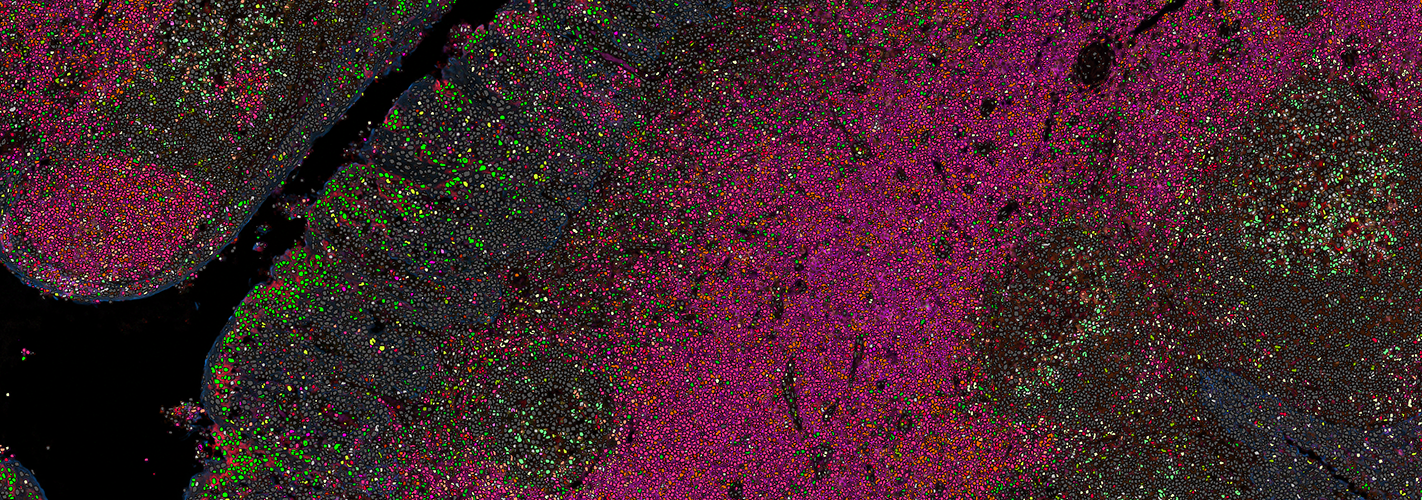

Visiopharm’s pioneering image analysis tools support thousands of scientists, pathologists, and image analysis experts in academic institutions, biopharmaceutical industry, and diagnostic centers. AI-based image analysis and tissue mining tools support research and drug development research worldwide, while CE-IVD APPs support primary diagnostics. With the most advanced and sophisticated artificial intelligence and deep learning, Visiopharm delivers tissue data mining tools, precision results, and workflows.